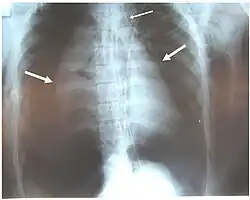

Pneumotórax bilateral (setas grandes), pneumomediastino (seta pequena) e enfisema subcutâneo em um paciente com ruptura completa do brônquio direito. O vazamento de ar foi contínuo apesar da sucção.[1]

Os sinais e sintomas variam dependendo da parte da árvore traqueobrônquica afetada e da gravidade do dano.[6] Não há sinais diretos de lesão traqueobrônquica, mas certos sinais sugerem a lesão e aumentam a suspeita clínica.[8] Muitos sinais e sintomas também estão presentes em lesões com mecanismos semelhantes, como pneumotórax.[9] Dispneia e dificuldade respiratória ocorrem em 76–100% dos casos, e hemoptise foi observada em até 25%.[10] Contudo, lesões traqueobrônquicas isoladas raramente causam sangramento abundante; se presente, é provável que seja devido a outra lesão, como ruptura de um grande vaso sanguíneo.[2] O paciente pode apresentar disfonia ou redução dos sons respiratórios, e taquipneia é comum.[3] Tosse pode estar presente,[11] assim como estridor, um som respiratório agudo anormal que indica obstrução das vias respiratórias superiores.[12]

Danos às vias respiratórias podem causar enfisema subcutâneo (ar preso na hipoderme da pele) no abdômen, tórax, pescoço e cabeça.[2] O enfisema subcutâneo, presente em até 85% dos casos,[10] é particularmente indicativo da lesão quando ocorre apenas no pescoço.[13] Ar preso na cavidade torácica fora dos pulmões (pneumotórax) ocorre em cerca de 70% dos casos.[4][10] Evidência forte de lesão traqueobrônquica é a falha do pneumotórax em resolver mesmo com a colocação de um sistema coletor de drenagem pleural ou mediastinal para remover o ar; isso indica vazamento contínuo de ar do local da ruptura.[11] Ar também pode ficar preso no mediastino, o centro da cavidade torácica (pneumomediastino).[4] Se o ar escapa por uma lesão penetrante no pescoço, pode-se confirmar o diagnóstico de lesão traqueobrônquica.[10] O sinal de Hamman, um som de crepitação sincronizado com o batimento cardíaco, também pode acompanhar a lesão.[14]